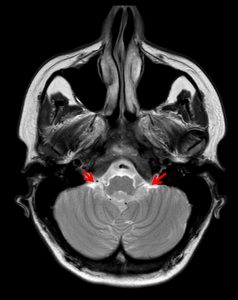

Τα επενδυμώματα ανήκουν στα γλοιώματα και αναπτύσσονται τυπικά εντός ή πλησίον του επενδύματος του κοιλιακού συστήματος του εγκεφάλου. Η πιο συνηθισμένη θέση είναι η περιοχή της παρεγκεφαλίδας (Εικόνα 1 & 2).